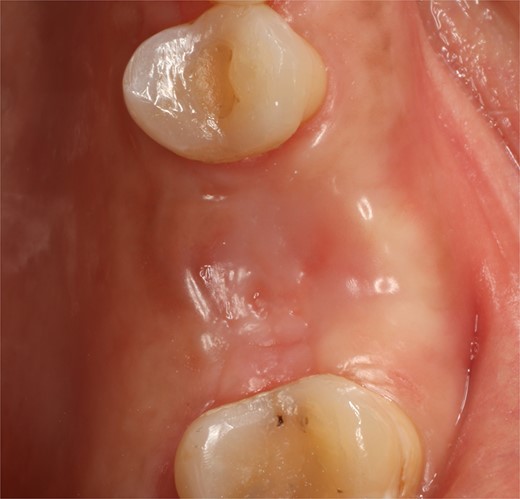

A 56-year-old female patient without any systemic diseases was referred by otolaryngology for evaluation by oral surgery due to presenting pain on the left side of the face for two weeks. The patient’s first molar presented a wide restoration (Fig. 1). This molar had undergone endodontic treatment some years ago. The CT scan showed a hyperdense left maxillary sinus almost entirely with loss of continuity of the maxillary sinus floor at the level of the left upper first molar involving the furcation zone, it is evident an oroantral communication of 7 mm (Fig. 2). The patient referred to spontaneous pain during chewing. Based on the CT scan and the clinical findings, pharmacological management was indicated with oral antihistamine 10 mg every 24 hours for 10 days, Moxifloxacin 400 mg every 24 hours, and scheduled extraction with oroantral communication closure with collagen sponge on the third day after starting the antibiotic, which will be used for a total of 10 days. The patient agreed to sign an informed consent file to make the technique to extraction and close the oroantral communication.

Following local anesthesia, an intrasulcural incision was made from the distal surface of the premolar, continuing through the sulcus to the mesial surface of the second molar in the vestibular and palatal surfaces. After the molar was extracted, granulation tissue was observed inside the socket that continued inside the maxillary sinus (Fig. 3); The socket was scaled, washed, and rinsed with physiological saline. The labial and palatal mucoperiosteal flaps are raised with full-thickness tunneling of the tissue, exposing the labial and palatal bone plates to allow a space for the ribose-crosslinked collagen membrane that will be used for socket closure. A 5 mm × 10 mm × 10 mm collagen sponge with hydroxyapatite and ribose was used, which was taken to the alveolus without hydration so that it absorbs as much blood as possible. It is important that the sponge has retention in the alveolus so that it does not displace within the maxillary sinus and is positioned at the same level as the remaining bone crest. A collagen membrane crosslinked with ribose was placed from buccal to palatal under the tunneled tissues (Fig. 4). A 5–0 absorbable monofilament suture was used, another layer of the collagen membrane was used in the occlusal area that was exposed, and two horizontal mattresses were sutured to give stability to the biomaterials (Fig. 5).